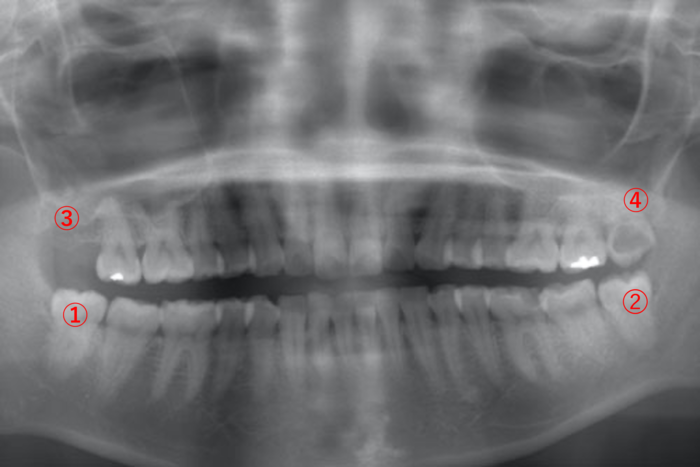

| 主訴 | 左下の親知らず(画像➁)が1週間前から急に腫れ始めて、痛みが強くて眠ることもできなくなった。 |

| 歯ブラシ | 現在妊娠中で、つわりにより奥まで歯ブラシを入れるのが困難な状態 |

つわりで親知らずまでキレイに磨くことができず、歯ぐきが腫れてしまったうえに腫れた歯ぐきを噛んでしまい、もっと腫れることになってしまった、とても辛いケースです。

こちらのレントゲン写真は、妊娠される前に撮影しました。

妊娠中は、抗生物質の服用をなるべく避けたいです。痛み止めもロキソニンやボルタレンは服用できないので、カロナールなどに限られます。患者さまも赤ちゃんへの影響を考え、薬は飲みたくないと言っています。

そこで、局所麻酔は、通常使用する量であれば胎児への問題は、少ないといわれていることから今回は、局所麻酔をかけて腫れている歯ぐきを切除し、後日、消毒しました。その後は、体調を優先に親知らずの歯ブラシや他の歯のクリーニングに通っていただき、出産後に親知らずを抜くことになりました。妊娠中に親知らずを抜くこともできましたが、やはり母体と赤ちゃんへの影響を考えると無理して抜歯するのではなく、歯ぐきの炎症を出来るだけ小さくするという選択をしました。

画像⑤の大きな虫歯は、今後痛みが出ると判断し、なるべく早く治療しました。

尚、妊娠中は、ホルモンのバランスが崩れやすいので、歯ぐきは非常に腫れやすく、出血しやすい状態となります。これは妊婦さんの特徴ですので、妊娠をする前に親知らずを抜いておくことや歯ブラシで上手に歯を磨くことをマスターしておくことをお薦めします。

|---|---|

| 主訴 | 歯並びが悪くならないように出来るだけ早く親知らずを抜きたい。 |

| 歯ブラシ | 非常にブラッシングが丁寧でキレイに磨かれている。 |

患者さまの1番の心配事は「親知らずが生えることで、小さい頃からしている歯列矯正に影響を及ぼすのではないか、歯並びが悪くなるのではないか」ということでした。

お口の中が非常にキレイに磨かれていて、今後、親知らずが虫歯や歯周病になる可能性は低いですが、まずは親知らずの根が神経にぶつかっていないことを確認して、問題ないようであれば親知らずを抜きましょうと説明しました。

下あごの親知らずが神経に接していないため抜歯は問題ないと考え、せっかくキレイに並んだ歯並びを崩したくないという患者さまの想いを尊重することとなりました。

まず、画像:①と②の親知らずを抜き、③と④の親知らずは生えてから抜くという手順になりました。

歯列矯正中の親知らず抜歯は、矯正の先生とも相談しながら、抜歯を検討するとよいでしょう。

| 年齢・性別 | 20歳・女性 |

|---|---|

| 主訴 | 虫歯が痛い |

| 歯ブラシ | あまり上手く磨けていない。全体的に汚れが付いている。 |

虫歯が痛いことを主訴に来院され、奥歯のほとんどに大きな虫歯がありました。歯医者さんで歯磨き指導を受けたこともなかったようで、まずは歯磨きの重要性と磨き方を説明しました。

虫歯治療が進むにつれ、患者さま本人もお口の中への関心が高まり、歯磨きも徐々に上達していきました。

虫歯治療が終わった段階で、半分埋まっている親知らず(画像①と②)は虫歯、歯周病のリスクが高いことを説明したところ、抜歯を希望されたため、抜歯しました。

年齢がまだ若く、親知らずの根の先が完全に完成していないため、神経に届いていない状態のうちに抜歯できて幸いだったと思います。